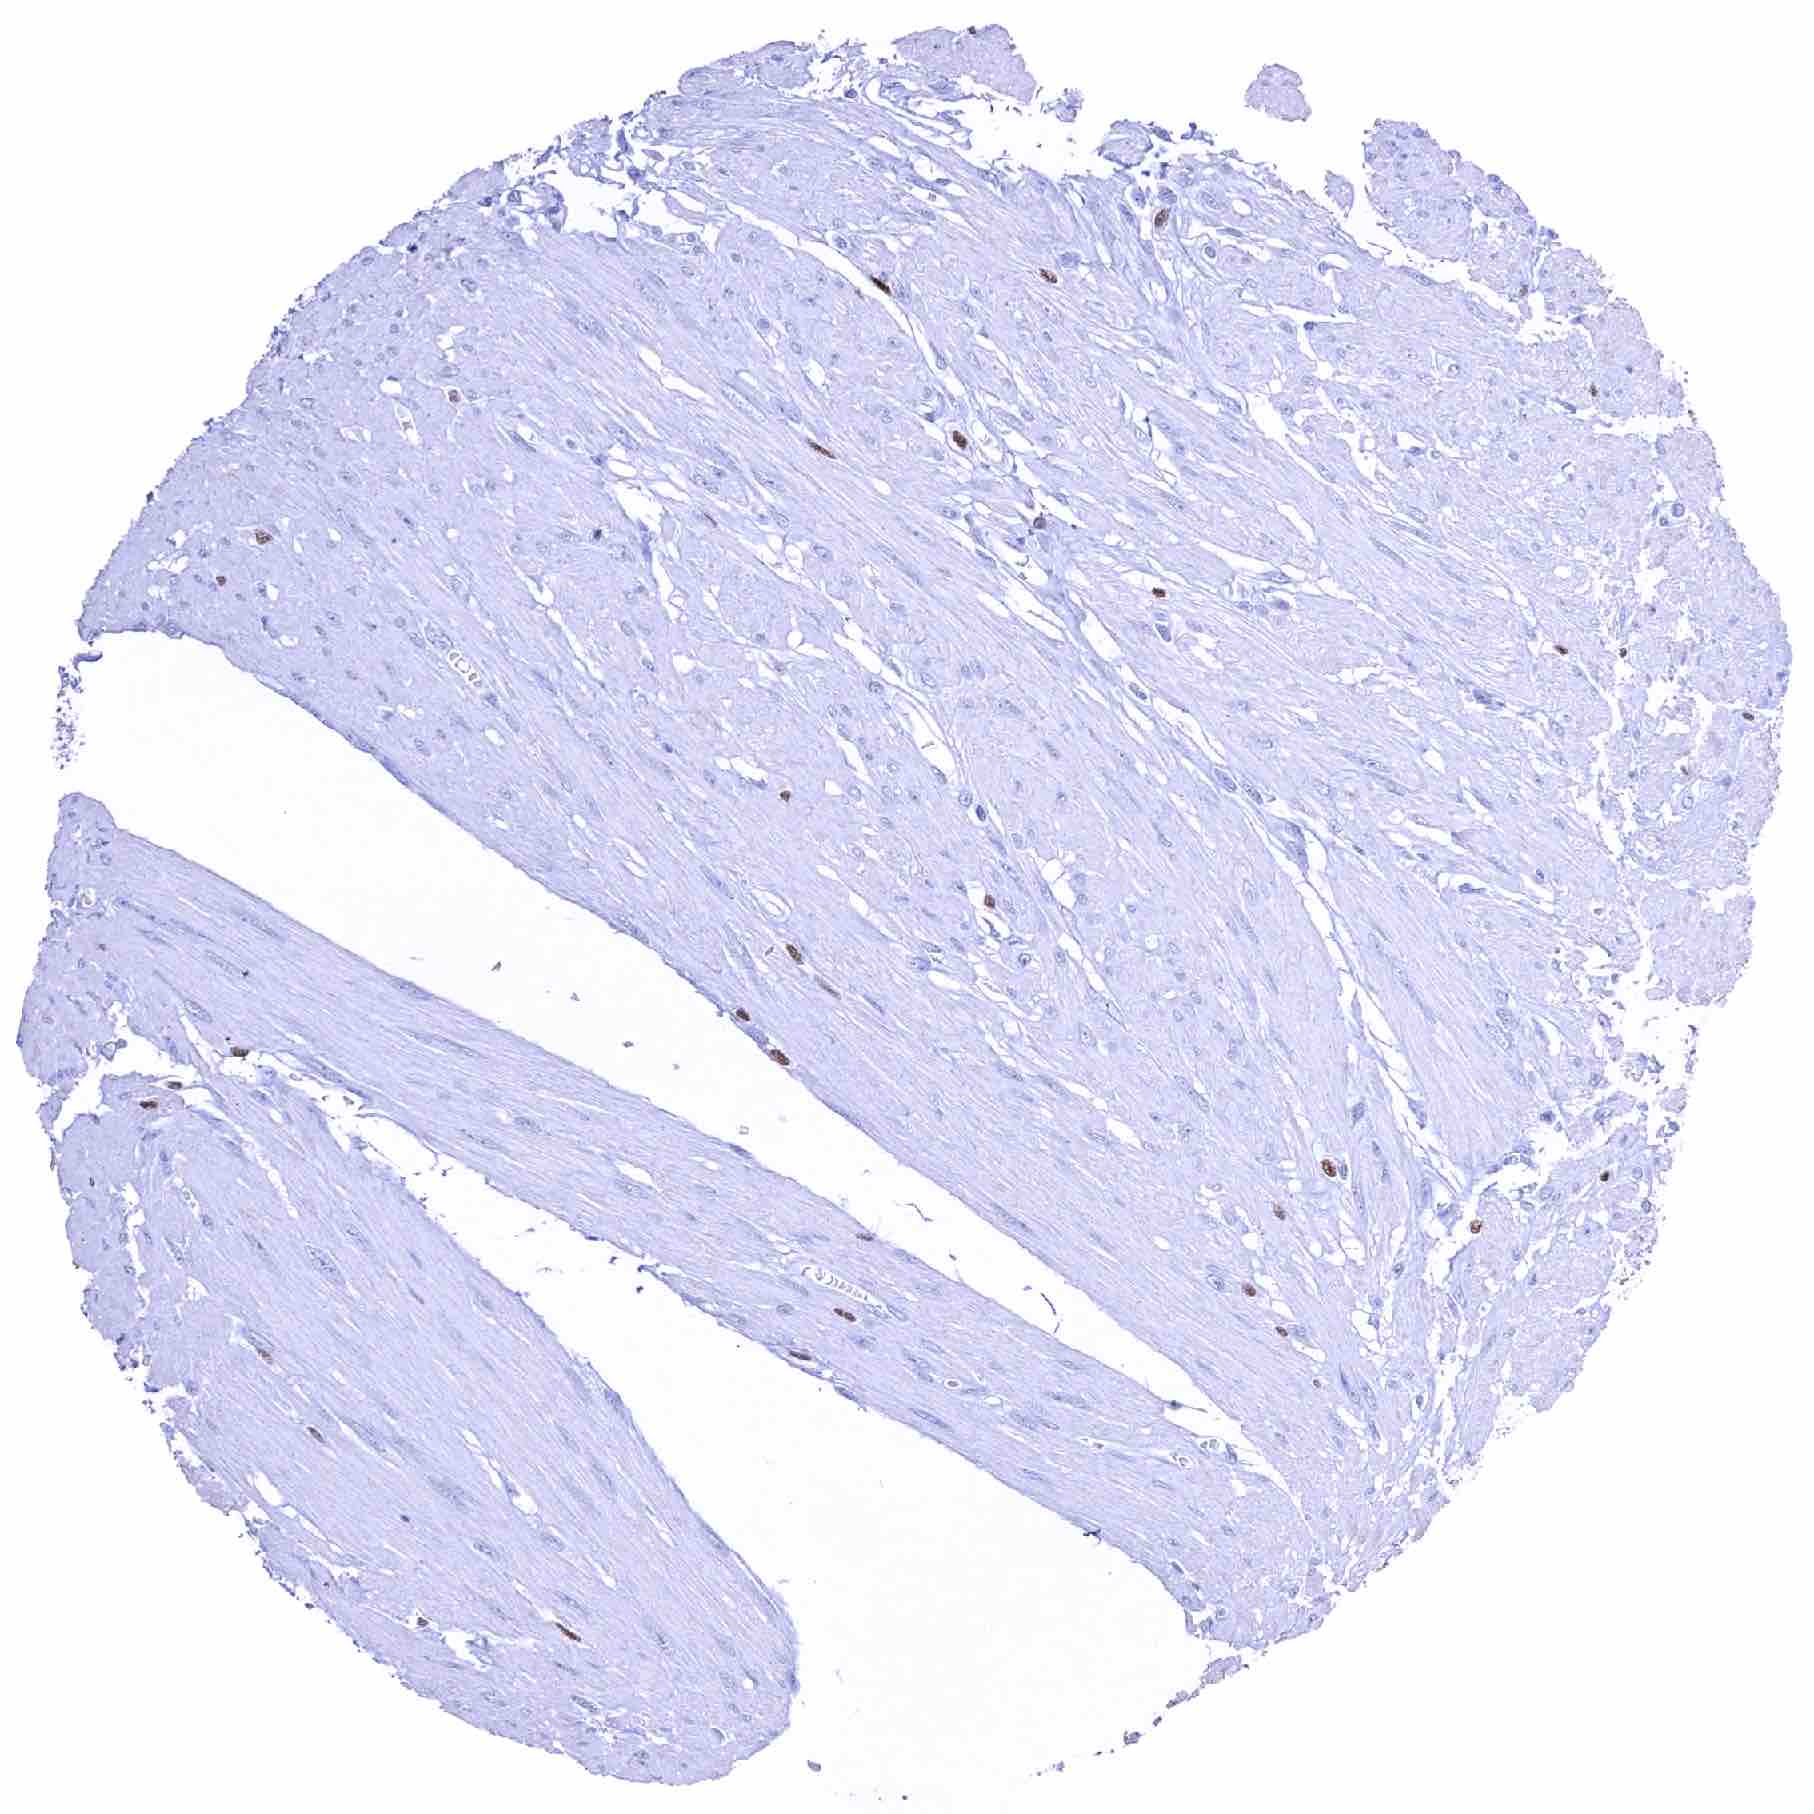

Aorta, media